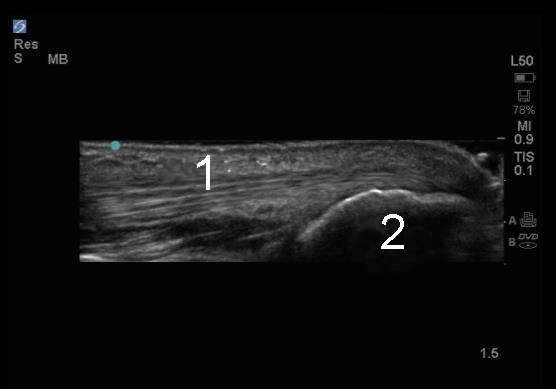

Elbow Triceps Tendon Long Axis Image

Triceps Tendon

Olecranon Process